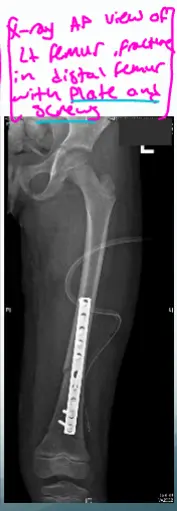

- X-ray AP view of Lt femur, fracture of distal femur with slab, Thomas splint

- X-ray AP view of Rt distal femur, presence of traction pin

- X-ray AP view of Lt femur, fracture in distal femur with plate and screws